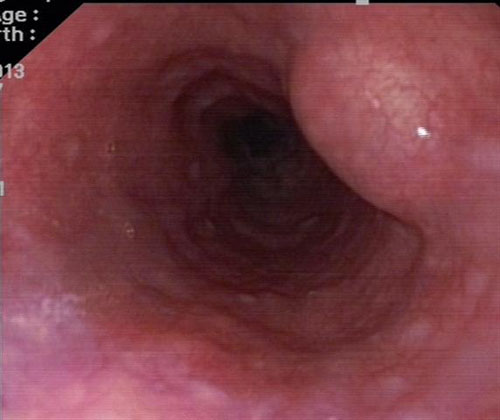

超声内镜见肿瘤起源固有肌层